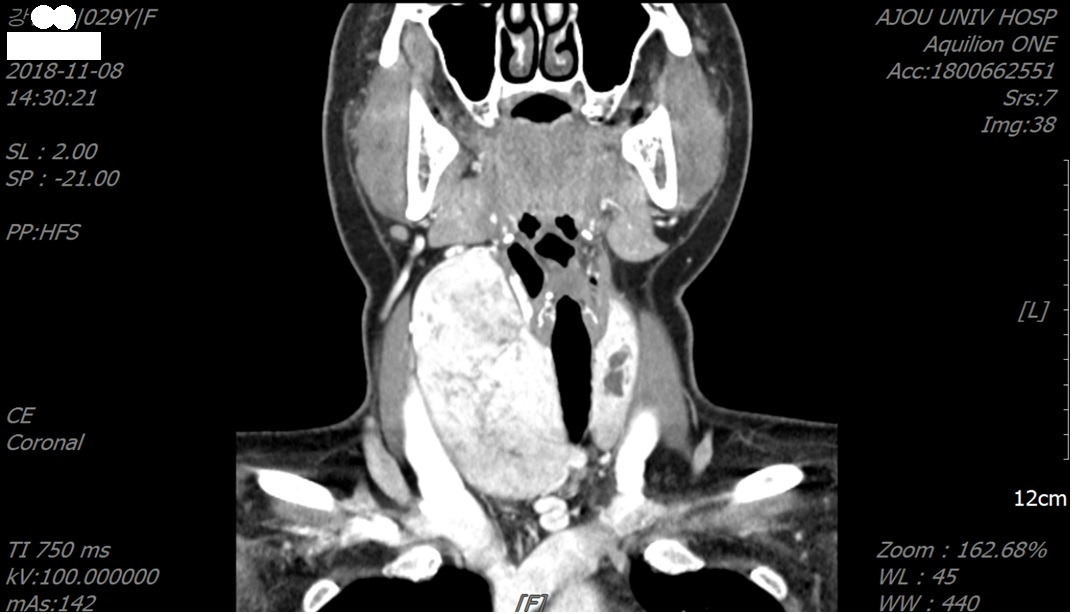

내 진료실에는 수려하였을 목에 툭 튀어나온 혹을 가졌거나, 며칠 후 절개선을 남겨야 하는 분들이 찾아온다. 커다란 혹도 오점이지만, 수술 후에 남는 절개선도 흠집이다. 그런데, 진료실에서 그 여성의 절실함은 지켜주지 못하는 의사에게 안쓰러움을 느끼지만, 안쓰러움은 미안함으로, 그리고, 결 다른 절실함으로 의사인 나에게도 다가왔다. 기존에 시행해 왔던 액와부 절개법은 갑상선, 또는 혹이 크거나, 갑상선 좌우 양 엽에 암이 있어서 완전절제 (R0 resection)을 하기 어려운 경우가 있기 때문이다. BABA는 이러한 환자들의 절실함을 해결해 주었다. 그림 2는 10cm가 넘는 갑상선 결절을 가진 환자를 BABA로 수술한 사람의 CT 사진이다. 혹이 크다 보니 수술시간이 길었으나, 그만큼 기억에 남아있다. 이 수고로움은 외래에 찾아오실 때마다 나에게는 추억의 편지로 남았다.

그림2